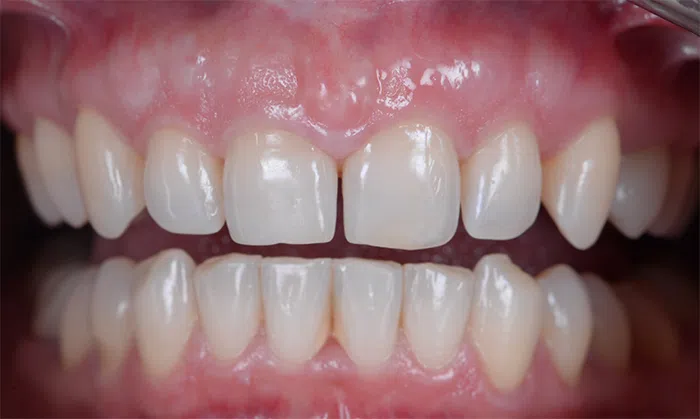

După

Caz de estetică dentară – Fațete ceramică presată E-Max

Provocarea acestui caz a fost în prepararea minim invazivă a dinților centrali rotați și a obține o formă și o culoare cât mai naturală, pacienta dorind un caz de estetică dentară ce să nu fie observabil.

Pacienta a beneficiat de corecție gingivala cu laser pentru uniformizarea asimetriilor gingivale, tratamente endodontice de canal sub microscop, obturațiile vechi (plombe) schimbate cu materiale de compozit cu particule nanoceramice, și fațete dentare din ceramică presată E-Max.

Termen de finalizare 2 săptămâni de la amprentarea finală.